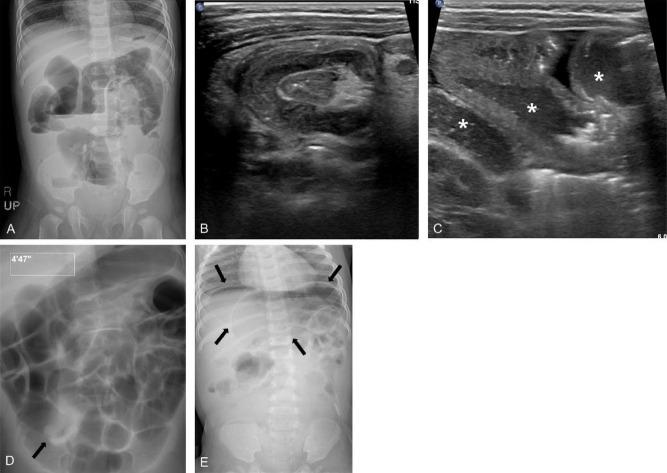

Intussusception involves an invagination of the proximal bowel into the distal bowel, with ileocolic intussusception being the most common type. However, a diagnostic delay can lead to intestinal ischemia, bowel infarction, or even death; therefore, its early diagnosis and management are important. The primary role of abdominal radiography is to detect pneumoperitoneum or high-grade bowel obstruction in cases of suspected intussusception, and ultrasonography is the modality of choice for its diagnosis. Nonoperative enema reduction, the treatment of choice for childhood intussusception in cases without signs of perforation or peritonitis, can be safely performed with a success rate of 82%. Enema reduction can be performed in various ways according to image guidance method (fluoroscopy or ultrasonography) and reduction medium (liquid or air). Successful enema reduction is less likely to be achieved in children with a longer symptom duration, younger age, lethargy, fever, bloody diarrhea, unfavorable radiologic findings (small bowel obstruction, trapped fluid, ascites, absence of flow in the intussusception, intussusception in the left-sided colon), and pathological lead points. This review highlights the current concepts of intussusception diagnosis, nonsurgical enema reduction, success rates, predictors of failed enema reduction, complications, and recurrence to guide general pediatricians in the management of childhood intussusception.

肠套叠是指近端肠管套入远端肠管,其中回结肠套叠是最常见的类型。然而,诊断延迟可导致肠缺血、肠梗死甚至死亡;因此,早期诊断和治疗至关重要。腹部X线摄影的主要作用是在疑似肠套叠病例中检测气腹或高位肠梗阻,超声检查是其诊断的首选方式。非手术灌肠复位是无穿孔或腹膜炎征象的儿童肠套叠的首选治疗方法,成功率为82%,可安全实施。灌肠复位可根据图像引导方法(荧光透视或超声检查)和复位介质(液体或气体)以多种方式进行。症状持续时间较长、年龄较小、嗜睡、发热、血性腹泻、影像学表现不佳(小肠梗阻、积液、腹水、肠套叠内无血流、左侧结肠肠套叠)以及病理性引导点的儿童灌肠复位成功的可能性较小。本综述重点介绍了肠套叠诊断、非手术灌肠复位、成功率、灌肠复位失败的预测因素、并发症及复发等方面的当前概念,以指导普通儿科医生对儿童肠套叠的管理。